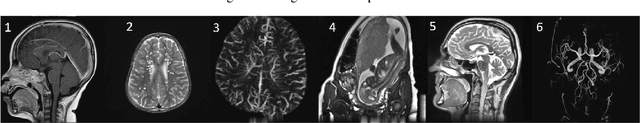

Abstract:Regularization plays a crucial role in reliably utilizing imaging systems for scientific and medical investigations. It helps to stabilize the process of computationally undoing any degradation caused by physical limitations of the imaging process. In the past decades, total variation regularization, especially second-order total variation (TV-2) regularization played a dominant role in the literature. Two forms of generalizations, namely Hessian-Schatten norm (HSN) regularization, and total generalized variation (TGV) regularization, have been recently proposed and have become significant developments in the area of regularization for imaging inverse problems owing to their performance. Here, we develop a novel regularization for image recovery that combines the strengths of these well-known forms. We achieve this by restricting the maximization space in the dual form of HSN in the same way that TGV is obtained from TV-2. We name the new regularization as the generalized Hessian-Schatten norm regularization (GHSN), and we develop a novel optimization method for image reconstruction using the new form of regularization based on the well-known framework called alternating direction method of multipliers (ADMM). We demonstrate the strength of the GHSN using some reconstruction examples.